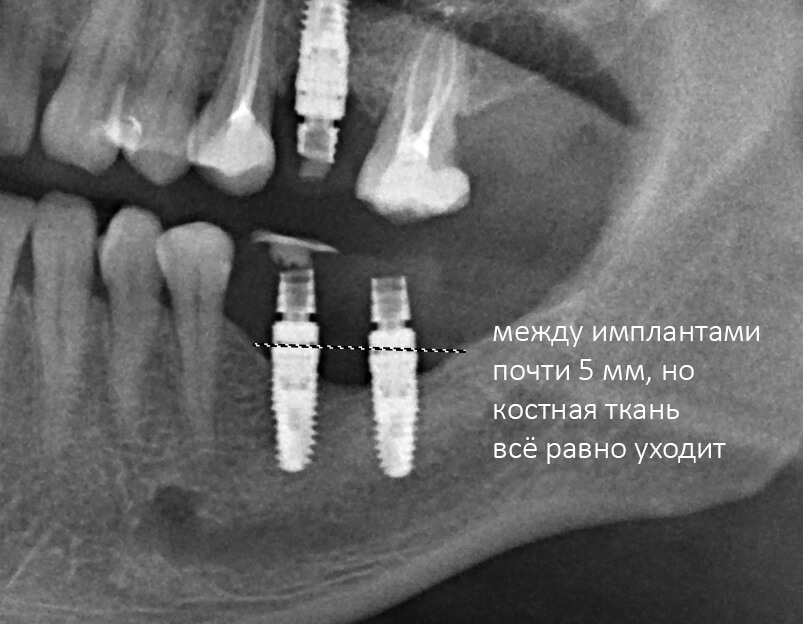

Рекомендации по установке имплантов. Для всех. Часть V.